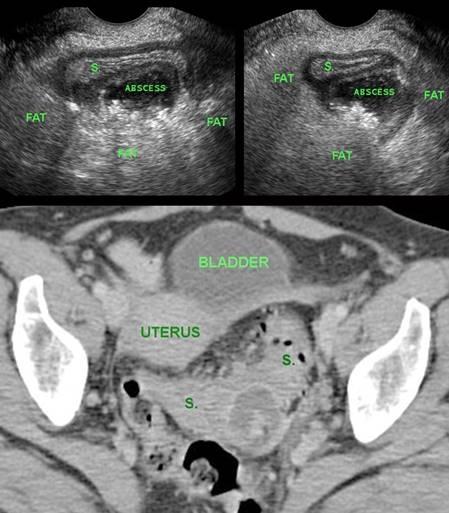

Bệnh nhân nữ, 37 tuổi, được nghi ngờ lâm sàng là áp-xe vòi trứng – buồng trứng, được chỉ định thực hiện TVUS.

Bác sĩ phụ khoa đã hội chẩn với bác sĩ chẩn đoán hình ảnh, người đã xác định đây là áp-xe nhỏ cạnh đại tràng, có thể có nguồn gốc từ túi thừa.

Chẩn đoán sau đó được xác nhận bằng chụp CT (S. = đại tràng sigma).